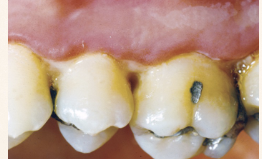

Describe the tissue contour in this image?

Cratered papilla